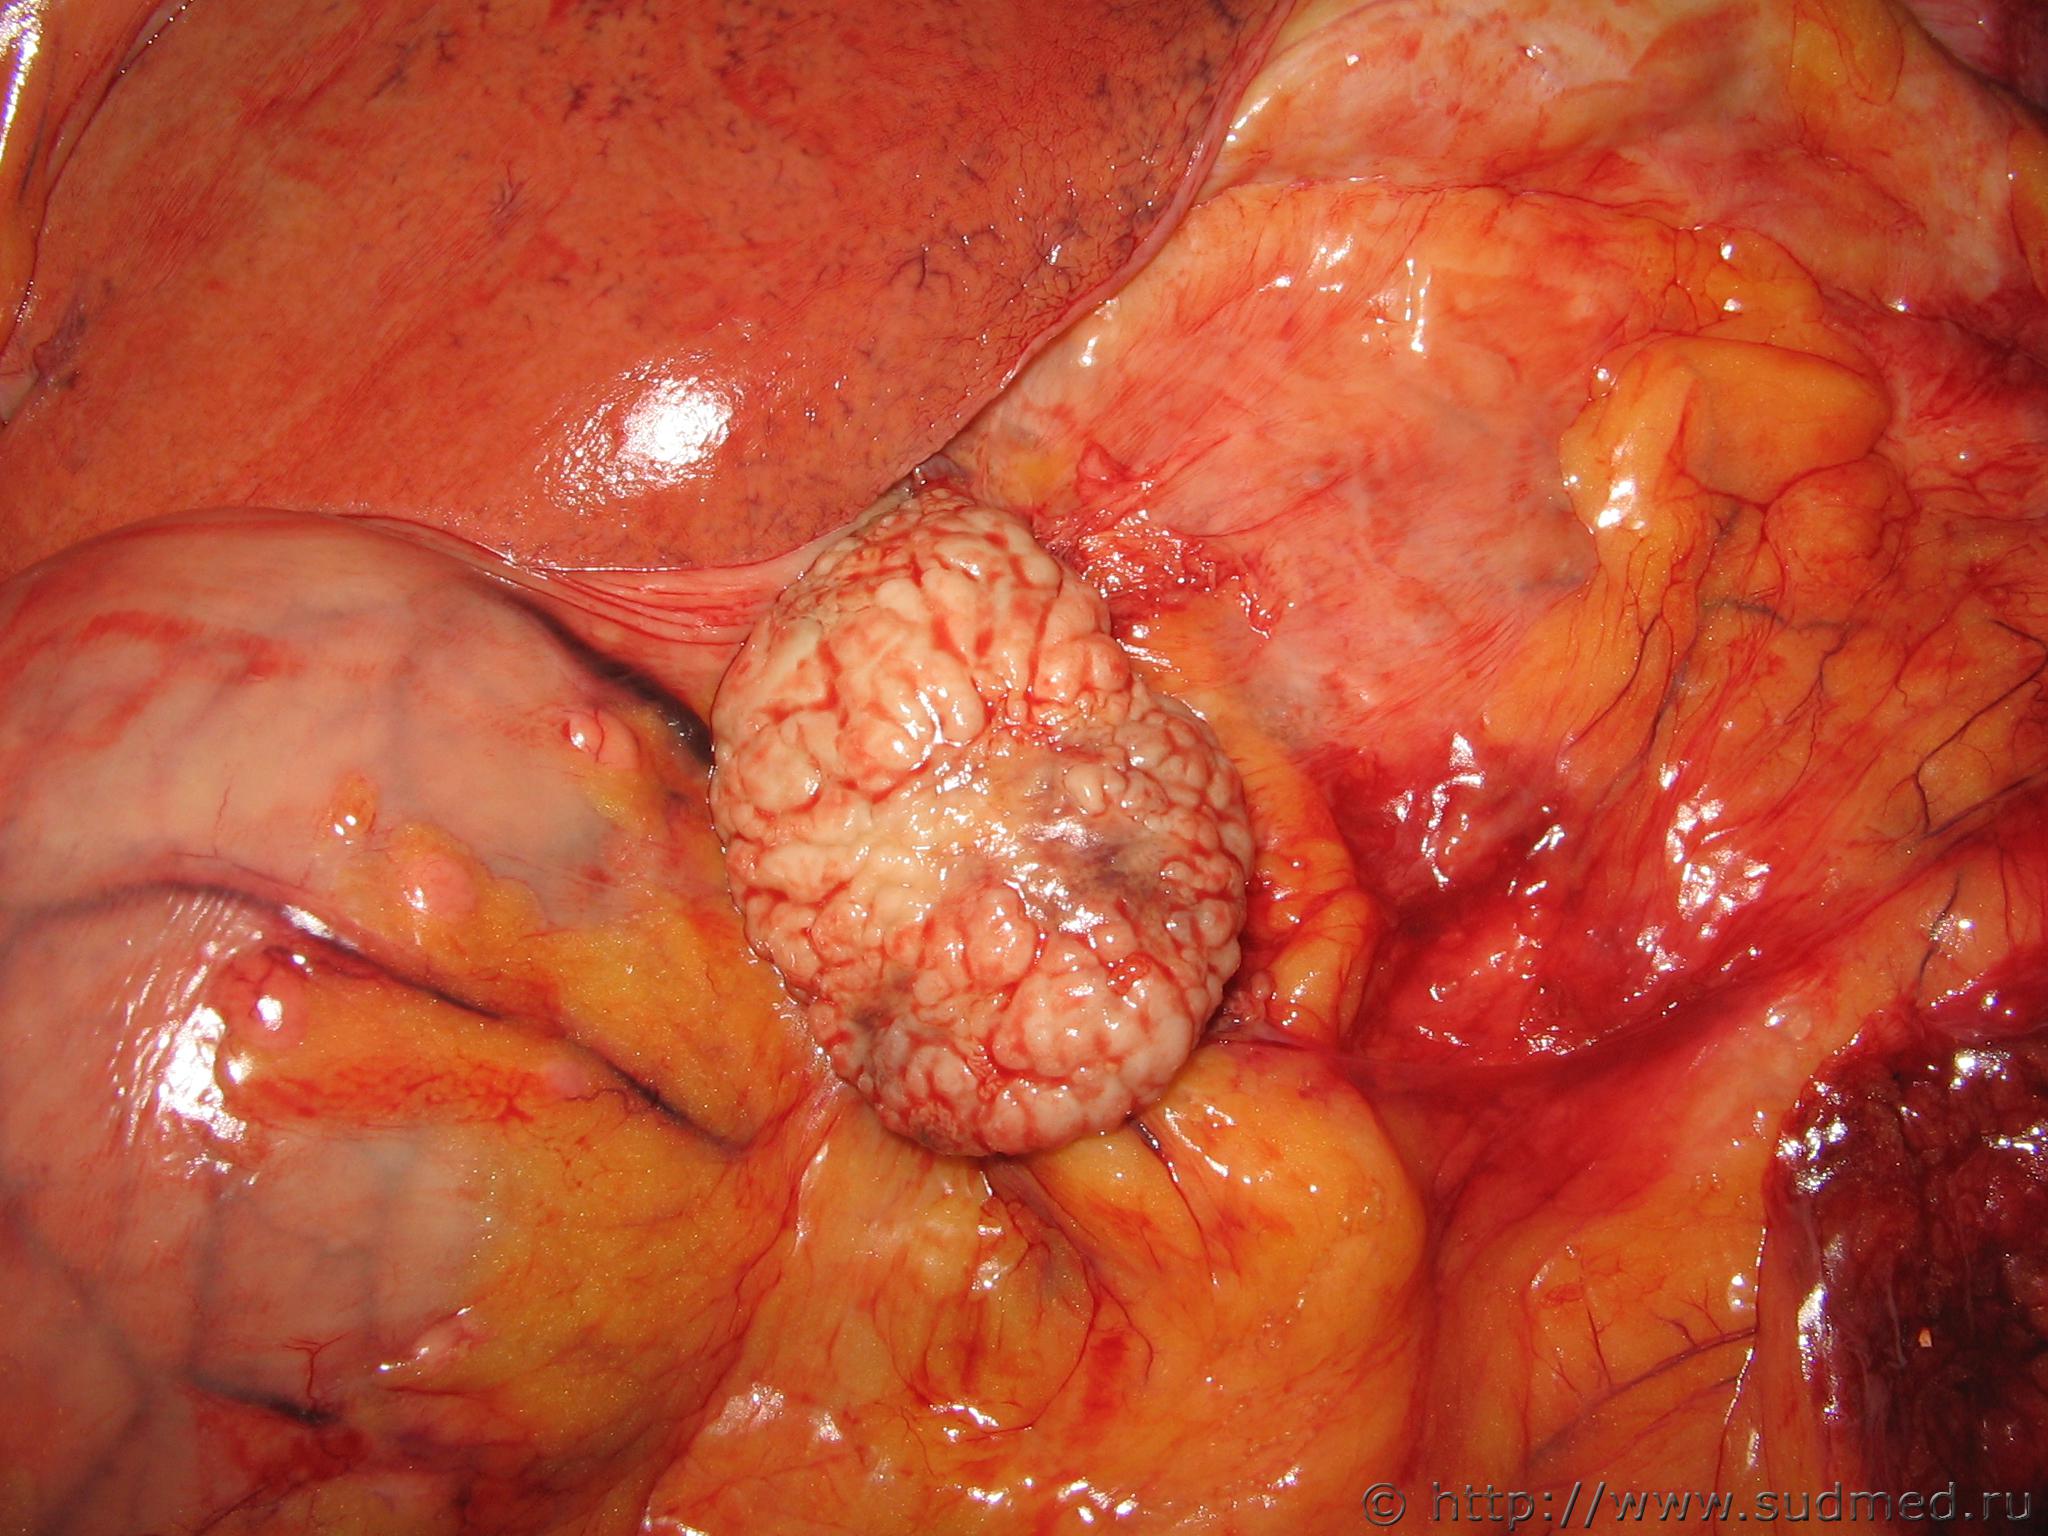

Поликистоз обеих почек.

Мужчина, 51 года, наследственный поликистоз обеих почек.

Панкреонекроз.

Вскрывали сегодня женщину 26 лет с алкогольной нейропатией. Вместо поджелудочной железы было образование 14х9х7, заполненное зеленоватым кашицеобразным содержимым.